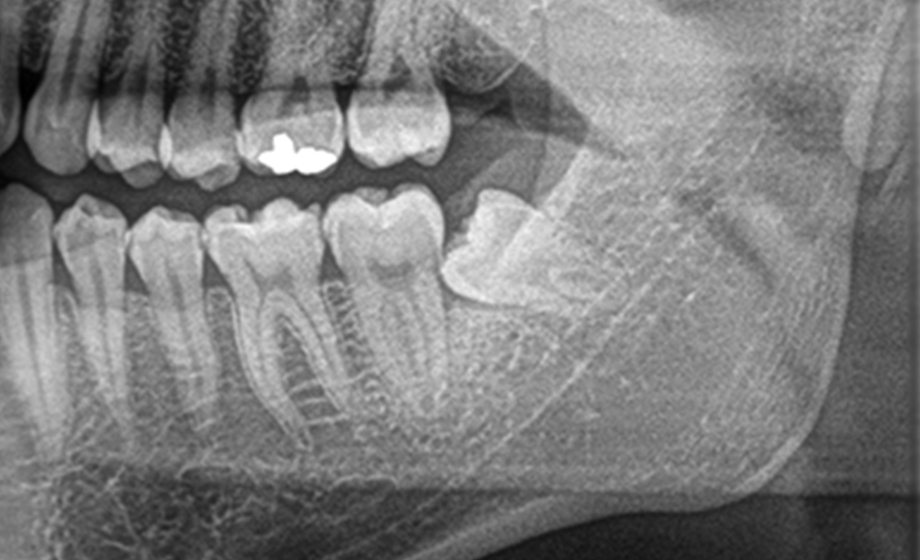

上記は、保険内治療でレジン充填治療(白い詰め物治療)を行った時の写真です。

治療時は口腔内カメラを活用し、治療前、治療中、治療後の状態を出来るだけ分かりやすくお伝えしています。